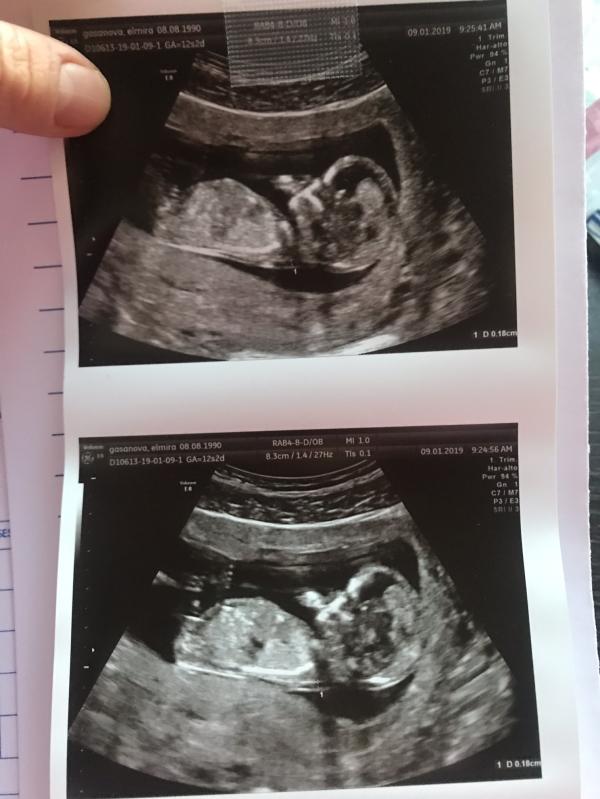

Второй ребёнок так яро сосал палец на скрининге первом😅Вика у нас на всех УЗИ подкладывала просто ручку к личику и до сих пор спит так😁 По ходу кто-то будет любитель пальчиков ❤️

Вообще сегодня и вчера чувствую толчки и движения( 15 недель), это так мило как то забыла быстро после первой😊 Чувствую себя нормально ,но по утрам иногда может «вывернуть», с Викой такого не было ....Пол нам не сказали,надеемся на девочку😊